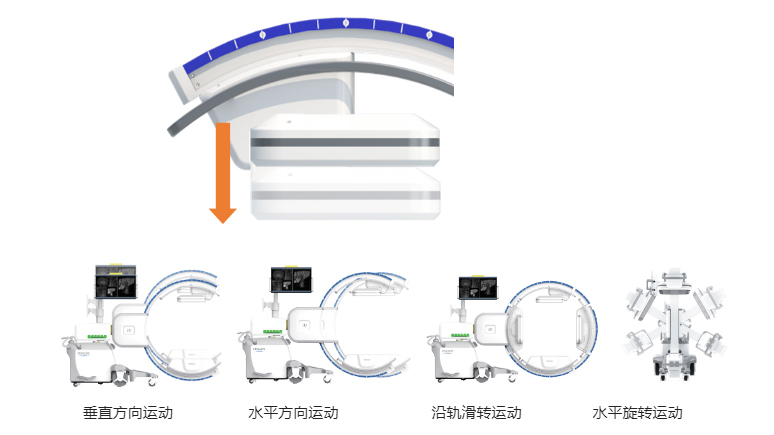

在C臂扫描过程中,始终保持拍摄主体处于射线束的中心,避免了序列图像采集过程中的横纵方向运动,减少相对运动造成的运动伪影。

平板垂直升降运动 便于术中微调平板与拍摄主体的距离,更加贴近病灶体,成像范围更大,图像更清晰。